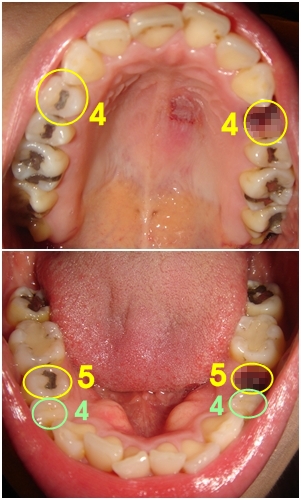

└▷ 처음 왼쪽 부분 먼저 발치했을 때 사진인데요~

원래는 상악, 하악 둘다 4번 치아를 발치할 예정이었으나..

하악은 멀쩡한 4번 치아를 살리고~ 충치 치료 받은 적 있는 5번 치아를 발치했어요~

5번 치아로 발치하니.. 웃을 때 발치한 부분이 덜 보여서~ 나름 괜찮네요 ㅋㅋ

└▷ 전부 다 발치하고 난 지금의 치아입니다.. 'ㅁ' (ㅎ ㅏ ~ 삐뚤삐뚤 민망한 치아.. ㅜㅠ 안습이네요~)